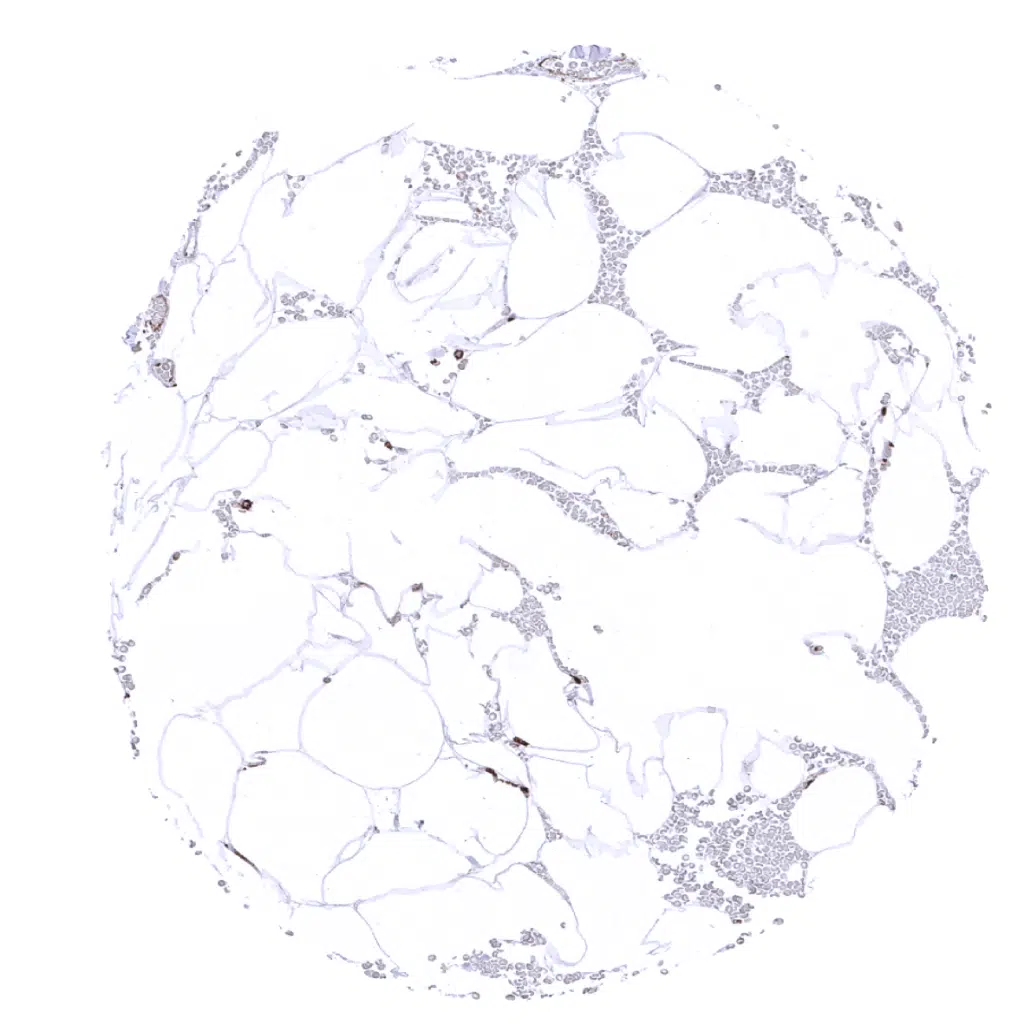

Fat

Lung: Intense HLA-DRa immunostaining of alveolar macrophages and alveolar capillaries.